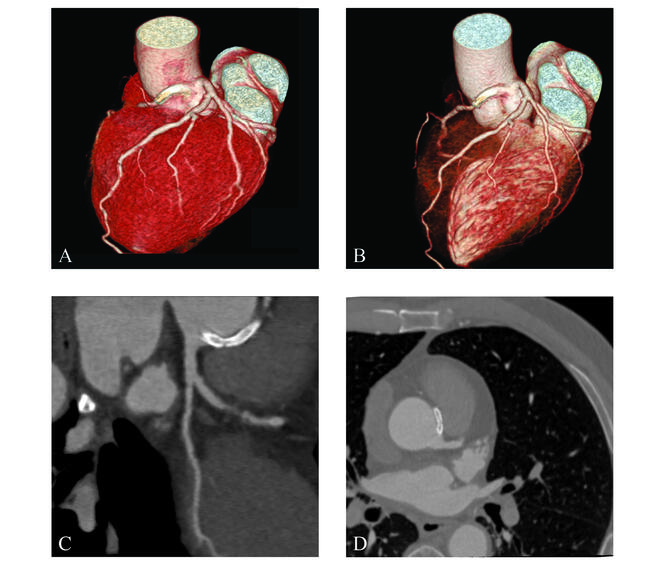

A 69-year-old man with unstable angina underwent coronary angiography showing no lesion in the left coronary artery and critical stenosis in the proximal right coronary artery (RCA) arising from the left sinus of Valsalva (Figure 1). Notably, selective RCA engagement was possible only with a guide-catheter extension (Video 1). Moreover, intravascular ultrasound (IVUS) revealed an intramural aortic course (IAC) of the proximal RCA (Figure 2, Video 2).